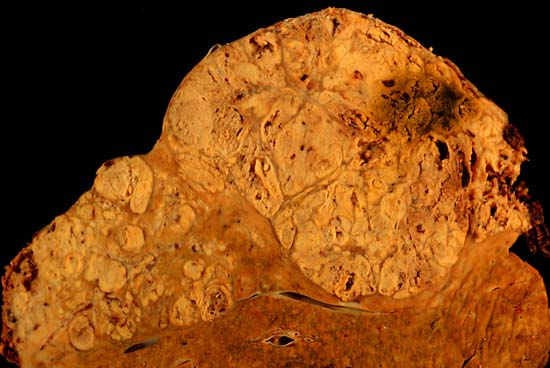

Hepatocellular carcinoma This specimen is from a 50ish woman who presented to the hospital with abdominal pain and ascites. The radiologist recovered what appeared to be whole blood on paracentesis. Cytological exam of the bloody fluid showed no evidence of malignancy. Liver function tests were abnormal, and serologic tests were positive for antibody to hepatitis C. The patient deteriorated rapidly and died within a few days. The autopsy showed this hepatocellular carcinoma occupying much of the volume of a cirrhotic liver. Furthermore, the tumor had invaded the diaphragm and ruptured into the peritoneal cavity, causing the bloody ascites.

The photo shows a view of a longitudinal slice taken through the full length of the liver.